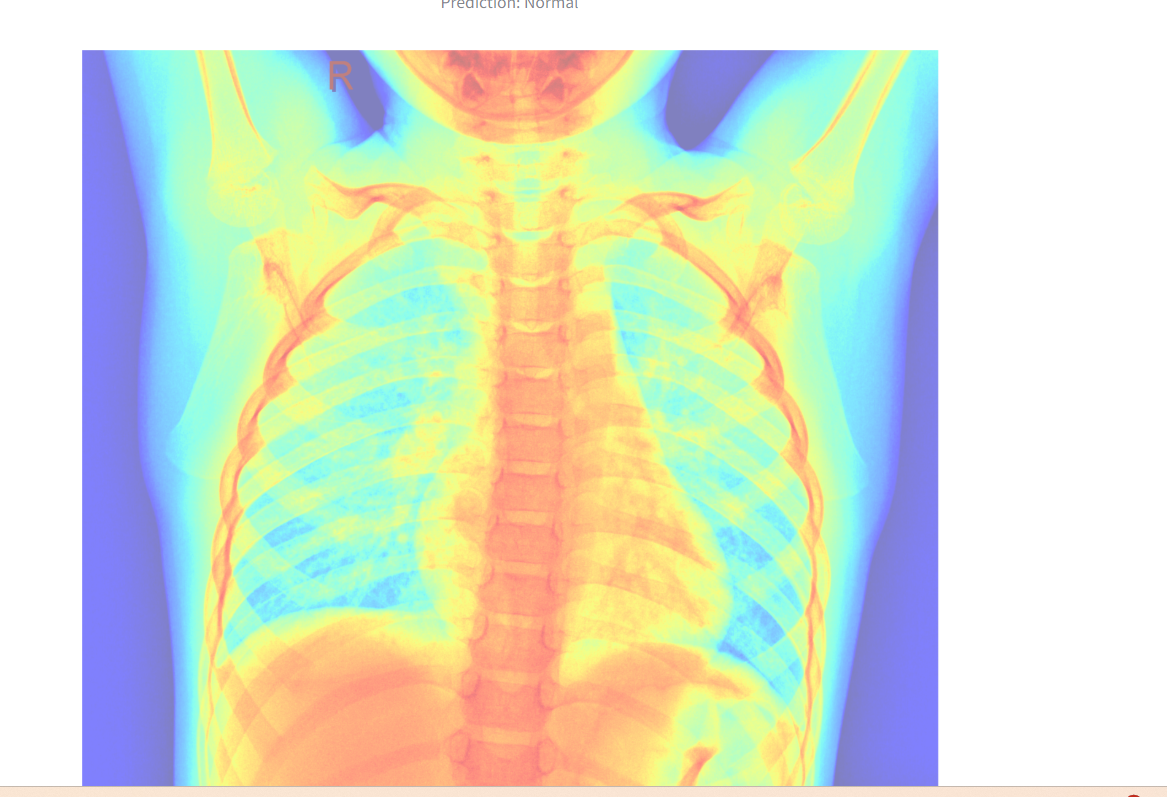

A heatmap overlay is generated for better interpretability.

The heatmap overlay

Visualization: The app enhances interpretability with a heatmap overlay.

Incorporating explainability tools such as Grad-CAM for enhanced interpretability.